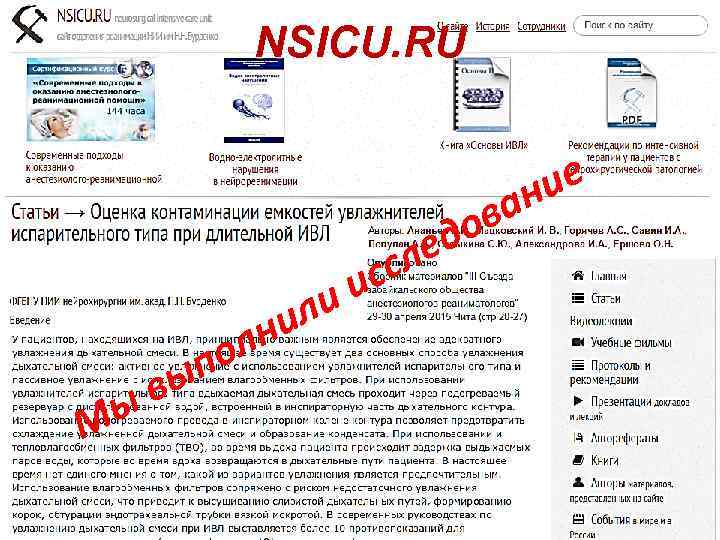

NSICU. RU ли ни ы М ол п вы сл ис ов ед ие ан

NSICU. RU ли ни ы М ол п вы сл ис ов ед ие ан

Мы выполнили исследование Дизайн • 5 пациентов длительная ИВЛ • БАЛ в день № 1 и в день № 5 ++ • ежедневные посевы из камеры увлажнителей Результат ? ? ?

Мы выполнили исследование Дизайн • 5 пациентов длительная ИВЛ • БАЛ в день № 1 и в день № 5 ++ • ежедневные посевы из камеры увлажнителей Результат ? ? ?

Мы выполнили исследование Дизайн 5 пациентов длительная ИВЛ БАЛ в день № 1 и в день № 5 ++ ежедневные посевы из камеры увлажнителей Результат Все посевы из камер стерильны!!!

Мы выполнили исследование Дизайн 5 пациентов длительная ИВЛ БАЛ в день № 1 и в день № 5 ++ ежедневные посевы из камеры увлажнителей Результат Все посевы из камер стерильны!!!

Колонизации микробами нет! Вода в камере увлажнителя остается стерильной При соблюдении: стерильная вода одноразовые камеры увлажнителей 5 дней-замена контура

Колонизации микробами нет! Вода в камере увлажнителя остается стерильной При соблюдении: стерильная вода одноразовые камеры увлажнителей 5 дней-замена контура